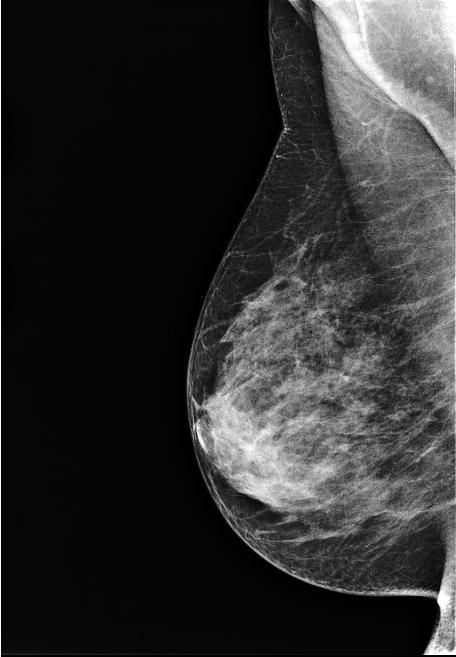

La mammographie est une exploration des seins utilisant les rayons X. Elle est réalisée sur un appareil spécifique situé dans un local exclusivement destiné à cet examen.

L’examen comporte 2 ou 3 clichés sur chaque sein. La compression du sein est nécessaire pour améliorer la qualité des clichés, donc l'efficacité du diagnostic radiologique. La compression est un peu désagréable. Elle est très rarement douloureuse. Si c'est le cas, la manipulatrice cessera immédiatement la compression.

La technique utilisée est celle de la radiographie, mais avec un faisceau de plus faible énergie (baisse du kilovoltage).